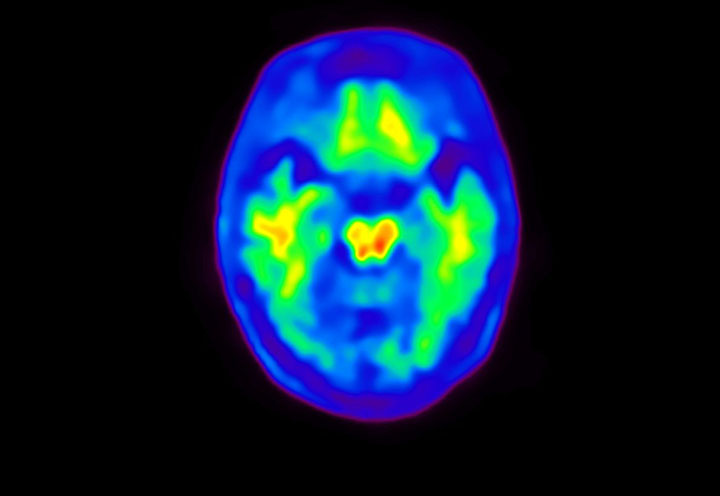

Head / Case4 : Amyloid

Sagittal

Courtesy : Kindai University Hospital

- Imaging protocol

- Injected dose: 3.21 MBq/kg, 18F-Flutemetamol

- Uptake time: 100 minutes

- Scan time: 20 minutes